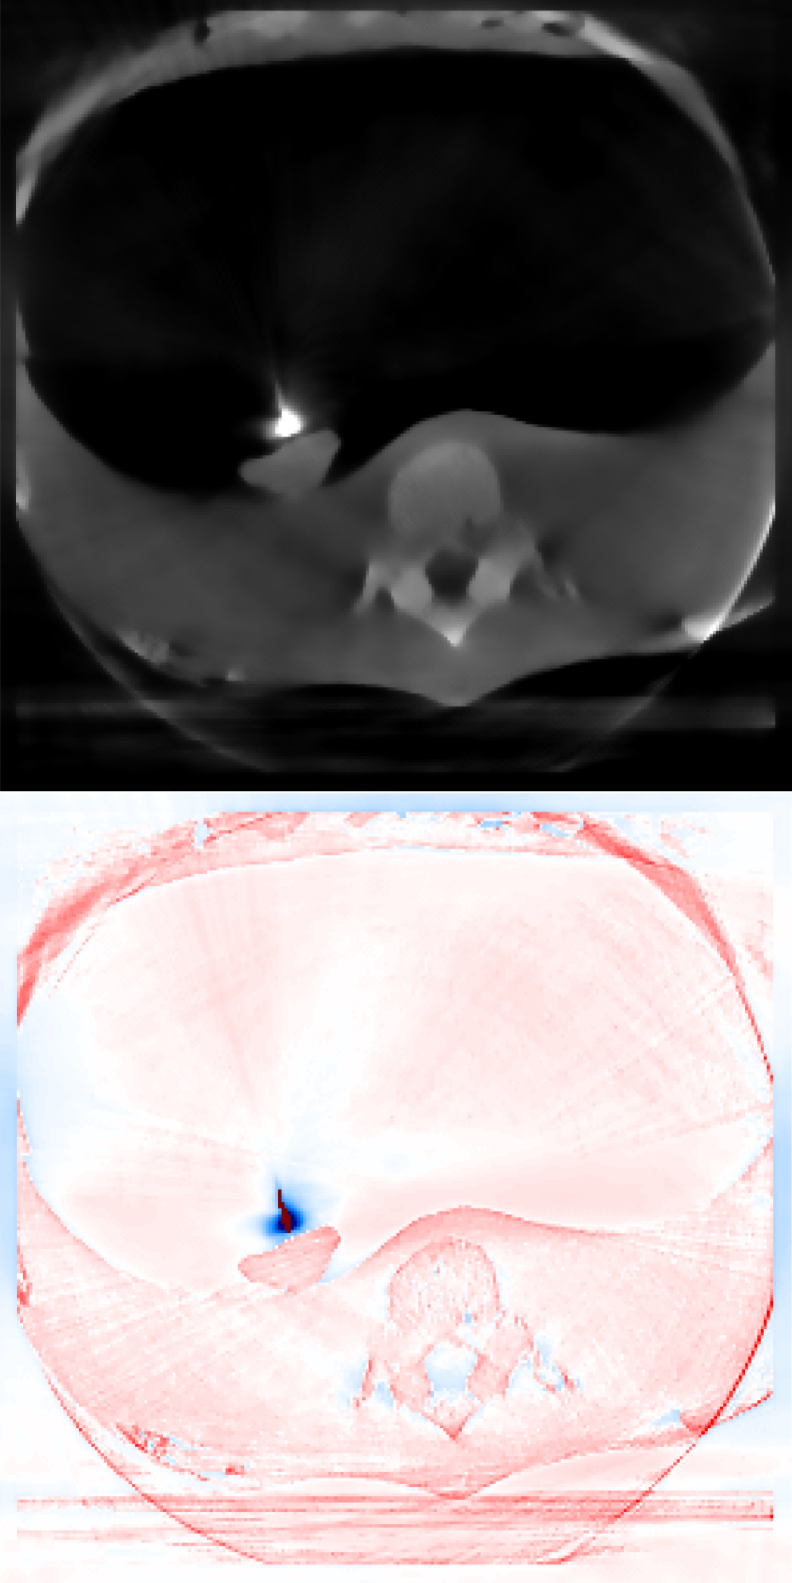

Figure 1 exhibits a slice of the reconstructed images using all the aforementioned algorithms. Here, (a) is the prior image 𝒙p\boldsymbol{x}_{p}, (f) is the ground truth, and the rests are the reconstructed images (top) with the corresponding reconstructions errors (bottom), all displayed using the same colorbar. Note that the error is just the difference between the reconstruction with respect to the ground truth image, so that high pixel intensity indicates inaccurate reconstructions and a fully black image would indicate a perfect reconstruction. This local error information is more informative than only displaying the error norms, or global error, since one can easily observe there is a high local difference between reconstructions.

Since this is a very undersampled dataset, FDK performs qualitatively poorly. Also for SIRT, and IRN-TV the quality drops significantly. The ASD-POCS-TV and ASD-POCS-PICCS are performing well, although a lot of texture information from the image is lost due to the smoothing process. However, the reconstruction time is higher than the other algorithms. The proposed algorithms perform better considering the available texture detail and the reconstruction time. Especially, the image in figure 1(h), IRN-PIPLE, is reconstructing the tumour better by preserving the texture information. Moreover, in figure 1(i), the tumour is more prominently visible due to the added TV regularization in the IRN-PICCS algorithm, however, with compromised original texture information of the image. Note that, for both proposed algorithms, the reconstruction time is in the range of 13 to 76 seconds only.

Figure 1: Reconstructed images using the digital head phantom data, with heavily undersampled projections (20 angles per set). The reconstructed images are shown in [0, 1]; difference images in [–0.5, 0.5].